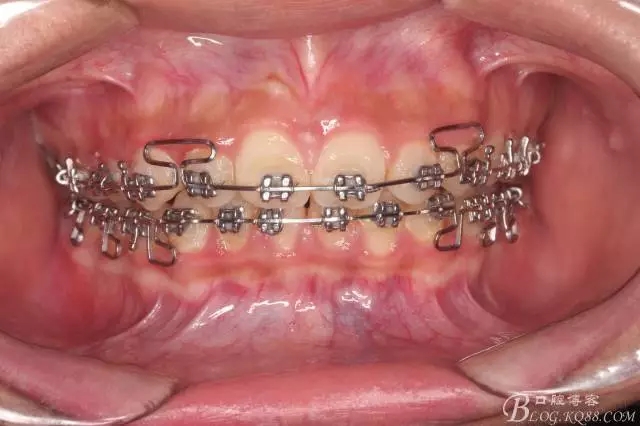

下頜配合多曲方絲,三角牽引,調(diào)整咬合。